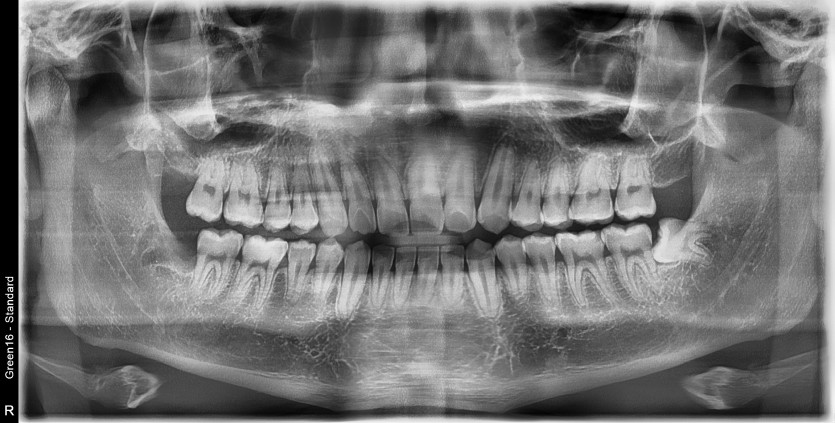

#38 사랑니 발치

구강 외과 전문의가 당일 발치했습니다.